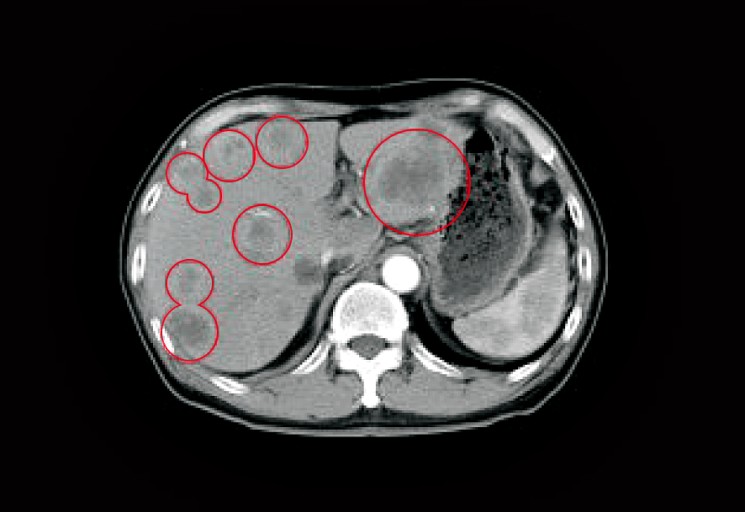

췌장염 증상 황달 + 진한 소변 + 연·회색 변(담즙 배출 장애 신호)

췌장과 담도는 해부학적으로 가깝습니다. 염증/부종이나 담석이 담즙 흐름을 막으면 피부·눈 흰자 노랗게(황달), 소변 짙은 갈색, 변이 옅거나 회색으로 바뀔 수 있습니다